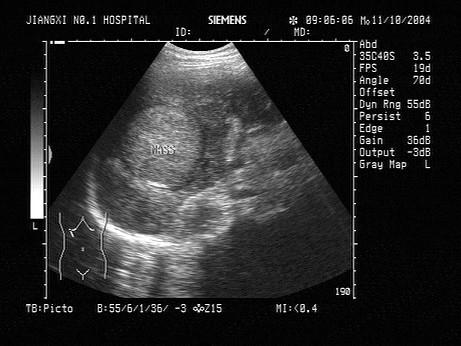

问题 根据肝脏声像图表现,最可能的诊断是?(?)

选项 A.原发性肝癌 B.转移性肝癌 C.肝脓肿 D.肝血管瘤 E.肝囊肿

答案 B